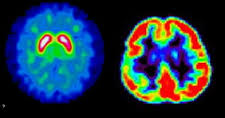

Ces décisions étaient attendues par l'ensemble des acteurs du secteur, en particulier les médecins radiologues qui verront leur activité impactée significativement. Elles portent sur deux champs distincts, le radiologie conventionnelle, l'imagerie en coupe et le TEP. Pour la première, c'est le facteur de majoration Z pour les actes de radiographie, représentant une modification de 21,8%, qui est supprimé et qui concerne uniquement les médecins radiologues. Le modificateur Y, quant à lui, est valorisé de 15,8%, ce qui profite à tous les actes de radiologie quelle que soit la spécialité du médecin qui les prend en charge.

Pour l'imagerie en coupe et le TEP, ce sont les forfaits techniques, comme l'on pouvait s'y attendre, qui se trouveront dévalués. Tous les forfaits techniques entrant dans ce champ sont désormais soumis à une baisse de 2% à compter du premier trimestre 2017, pour une économie de 16 millions d'€ dans les caisses de l'Assurance maladie. L'ensemble de ces dispositions génèreront une économie globale de 49.9 millions d'€ pour l'Assurance maladie, les dépenses totales remboursables, prise en charge des organismes complémentaires comprise, s'élevant à 59,9 millions d'€.